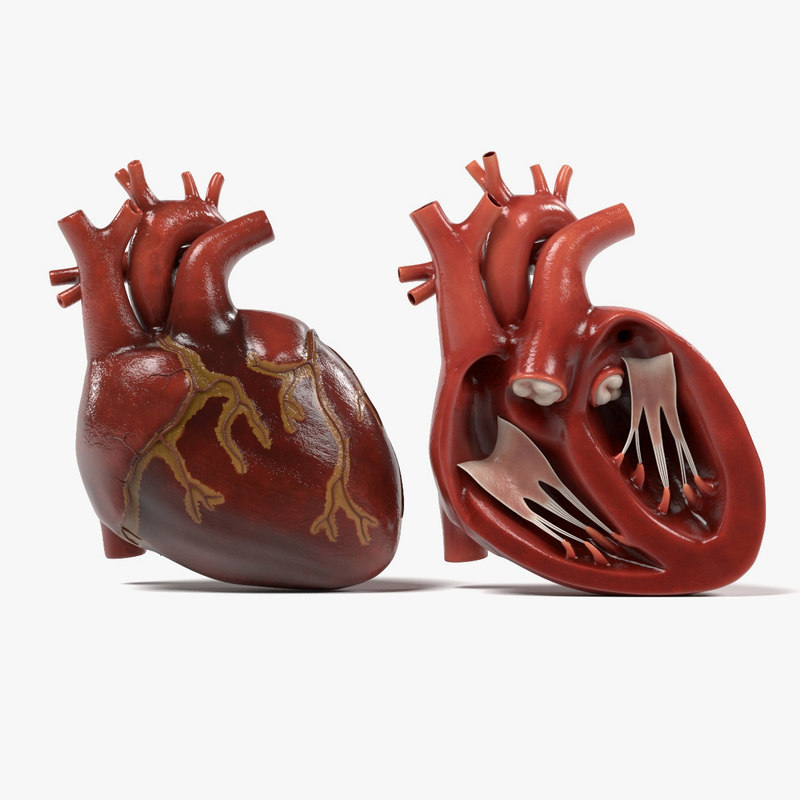

anatomy human heart 3d c4d  Modeled human heart section 3D model - TurboSquid 1657004

Modeled human heart section 3D model - TurboSquid 1657004  Heart by Rustamova on @DeviantArt | Anatomical heart art, Anatomy art, Heart drawing

Human Heart Section 3D model | CGTrader  human heart - internal anatomy 3d model